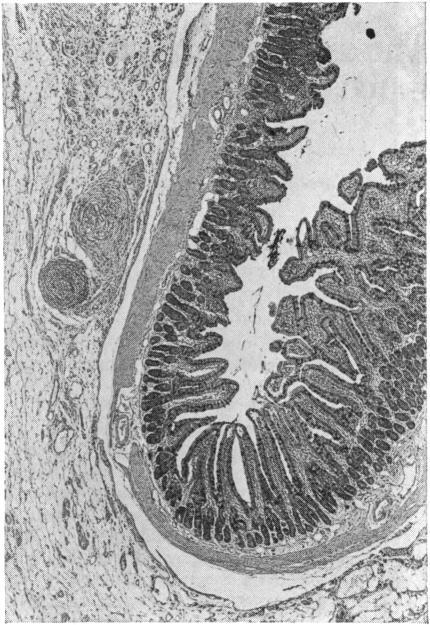

The dynamic structure of a flat small intestinal mucosa studied on the explanted rat jejunum.

Small pieces of jejunum with an intact blood supply were explanted to the anterior abdominal wall in rats. Six weeks after explantation the mucosa appeared totally flat in many areas, both histologically and under the dissecting microscope. The structure of the flattened mucosa was shown to be identical to that in coeliac disease with hypertrophied intervillous ridges. A dynamic study with tritium-labelled thymidine demonstrated a considerably increased turnover in the flat mucosa with some disorganization of cell production and migration.